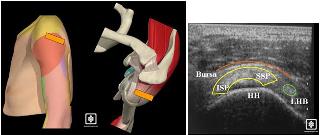

4. Supraespinoso.

Luego se le pide al paciente que coloque la mano en la cadera con el hombro en aducción y rotación interna tanto como sea cómodo para el paciente (similar a poner la mano en la posición del bolsillo trasero).

Teniendo en cuenta que el supraespinoso discurre en un plano a 30° con respecto al plano coronal del cuerpo, se debe colocar la sonda para una vista longitudinal del supraespinoso entre 30° y 60° con respecto al eje coronal del plano del cuerpo. Esto debería dar una buena vista del área de la huella de la tuberosidad mayor y la superficie articular superior de la cabeza humeral. Luego, la sonda se puede mover de anteromedial a posterolateral, es decir, desde el borde de ataque anterior del supraespinoso hacia el tendón del infraespinoso. El área más común para los desgarros del supraespinoso es en esta región.

A continuación, la sonda se gira 90° para obtener una vista transversal de los tendones del supraespinoso y la parte anterior de los tendones del infraespinoso (manguito superior). A continuación, la sonda se puede mover medial y lateralmente, así como anteromedial y posterolateral para obtener una buena impresión de esta zona. El movimiento medial adicional está limitado por el acromio.